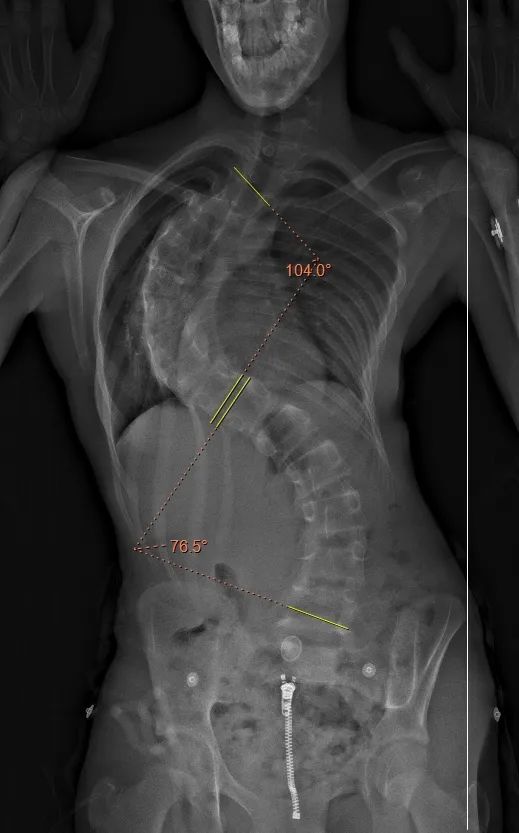

2024年,11岁英国女孩小D(化名)确诊青少年特发性脊柱侧弯。虽经支具治疗,病情却以惊人速度恶化:一年内主胸弯从40度发展至104度,伴随严重剃刀背畸形和呼吸功能障碍,严重影响生活。

△患者影像

主刀医生、新华医院脊柱中心主任杨军林教授指出,如此进展速度极为罕见。患者重度畸形且伴明显呼吸功能障碍,手术风险极高。通常需先行痛苦的头颅环牵引治疗以改善状况。但考虑患者对疼痛敏感且抗拒,经团队评估,创新性采用一期直接矫形手术方案,避免漫长牵引。

2025年7月,杨军林教授团队历经4小时高难度手术,成功实施截骨松解及去旋转技术,巧妙保留患者20%弯腰功能。术后脊柱畸形矫形率接近80%,患者“长高”8厘米,一周左右即可正常行走活动,可以自如地弯腰、后仰以及上下台阶。